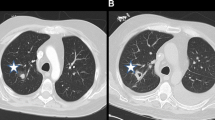

T2 *-weighted images of the kidneys need to be acquired using a Fast Low-Angle SHot (FLASH) sequence for six mice per group at required time point and 24 h following the administration of the USPIO contrast agent, compared with control mice.

The mice need to be centered in a 35 mm linear birdcage coil, and twelve 1 mm slices are acquired through the length of the body using a GE sequence (FOV = 5.0 × 3.2 cm2; TE = 10 ms; flip angle = 30; matrix size = 256 × 256; number of averages = 4).

Loading with ultrasmall particles of iron oxide (USPIO) serves as a contrast agent to label phagocytes. Thus, more iron indicates more phagocytes, which in turn indicates greater inflammatory reactions in infected kidneys.